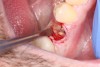

2. The remaining socket should be cleaned and curetted of all remaining granulation tissue or residual soft tissue present at the apex, especially with endodontically treated teeth (Figure 5).

Fig 5. Clean any granulation tissue out of the socket to create a clean wound free of debris.

Figure 5